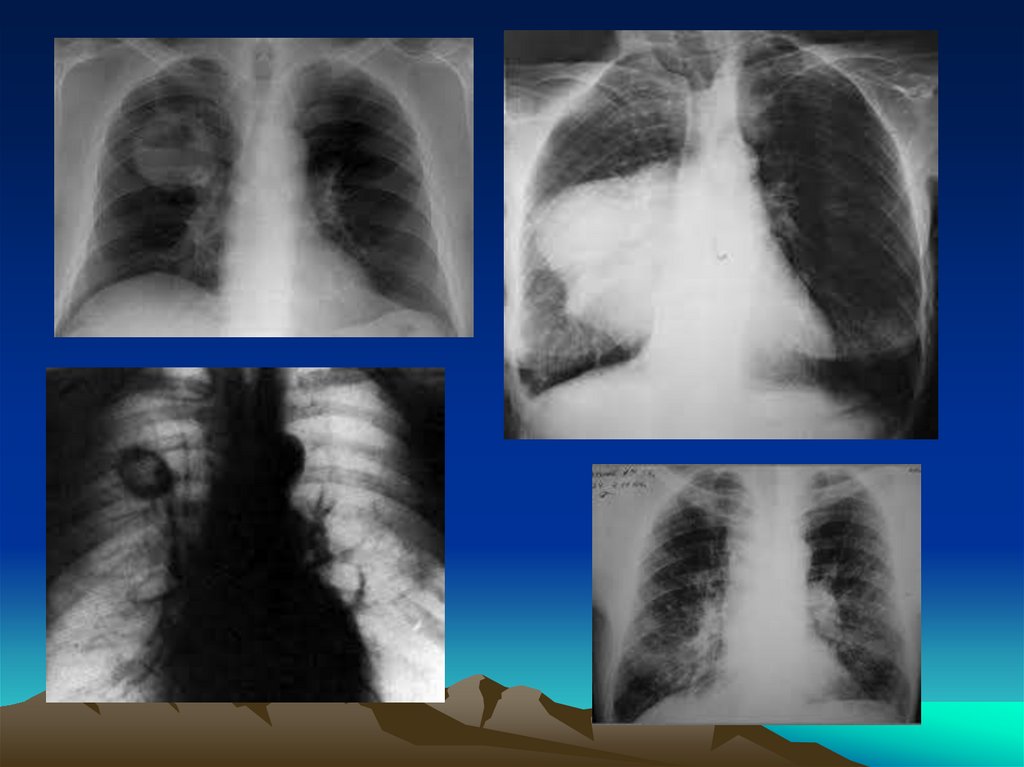

15.

16.

17.

18.

19.

Обзорная

рентгенография того

же больного

20.

21.

22.

23.